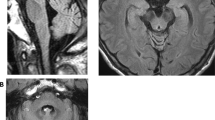

Among all 30 available participants, nine affected members were identified from four families of offspring in the third or fourth generation of this pedigree (Fig. 1A). The specific clinical features are shown in Table 1. The onset age ranged from 42–62 years and the duration of the disease varied from 1–25 years. All nine affected members presented core characteristics, namely difficulty in walking as an early feature, slow progression, followed by varying degrees of cerebellar ataxia, parkinsonism, and pyramidal signs (except IV-12, one-year course, no pyramidal signs). The severities of these three core clinical manifestations were closely related to the course of the disease. All patients over the eight-year course were confined to wheelchairs. The non-core features consisted of a variety of neurodegenerative manifestations. Among them, peripheral neuropathy and vertical gaze dysfunction were only found in the posterity's family D (III-6, III-7). Cognitive impairment, stridor, and cold hands were only found in the posterity's family C (IV-3, IV-5). Erectile dysfunction was found only in the posterity's family B (IV-13), and facial grimacing was found in the posterity's families A and C (IV-5, IV-12, IV-10). Four of the nine affected members underwent brain MRI scans, and all showed varying degrees of atrophy in the cerebellar cortex, vermis, and pons (Table 1, Fig. 2, Fig. S2). The axial T2-weighted images showed pontine-midline linear hyperintensities, similar to MSA-C in two affected members (IV-10, IV-15). SWI revealed hypo-intensities of the cerebellar dentate nuclei, basal ganglia, mesencephalic red nuclei, and substantia nigra (SN) in one affected member (IV-10), suggesting iron accumulation. ASL images showed decreased regional cerebral blood flow (rCBF) in the bilateral basal ganglia and the cerebellar dentate nucleus, followed by further deterioration over two years (IV-15), whereas there was reduction only in the dentate nuclei for the member at the pre-symptomatic stage (IV-10). Moreover, the following were all normal in the first proband (IV-15): cervical and thoracic spinal cord MRI scans; electrophysiological examinations of sensor- and motor-nerve conduction velocities; somatosensory-evoked potentials; and auditory-evoked potentials. These findings excluded cervical and thoracic spinal cord demyelination, peripheral neuropathy, deep sensory disorder, and auditory nerve damage.

Magnetic resonance imaging in the brain. Brain MRI scans were performed on four clinically affected family members (IV-3, IV-10, IV-13, and, IV-15), and one asymptomatic member carrying the CARS mutation (IV-23). A Marked atrophy of the pons, vermis, and B cerebellar cortex is shown in MRI scans from member IV-3; C Atrophy of the pons, vermis, and D cerebellar cortex with a pontine-midline linear hyperintensity on T2WI is shown for member IV-10. E, F A normal iron-induced SWI hypo-signal in the dentate nuclei and basal ganglia is shown in MRI scans from member IV-10. G, H Mild atrophy of the pons, vermis, and cerebellar cortex with lacunas in the pons is shown in MRI scans from member IV-13. I–K An iron-induced SWI hypo-intensity in the dentate nuclei, red nuclei, SN, and basal ganglia is shown in MRI scans from member IV-13. L Marked atrophy of the vermis, pons, and L–N diffuse cerebellar atrophy with N a pontine-midline linear hyperintensity on T2WI is shown in MRI scans from member IV-15. O Decreased regional cerebral blood flow (rCBF) in the bilateral basal ganglia (from IV-15) and P in the cerebellar dentate nucleus, Q with further deterioration over two years, is shown in MRI scans from member IV-15. R Decreased rCBF in the cerebellar dentate nucleus (from member IV-10). S Decreased rCBF in the left putamen and the head of the caudate nucleus (from V-23), T but not in the cerebellar dentate nucleus.